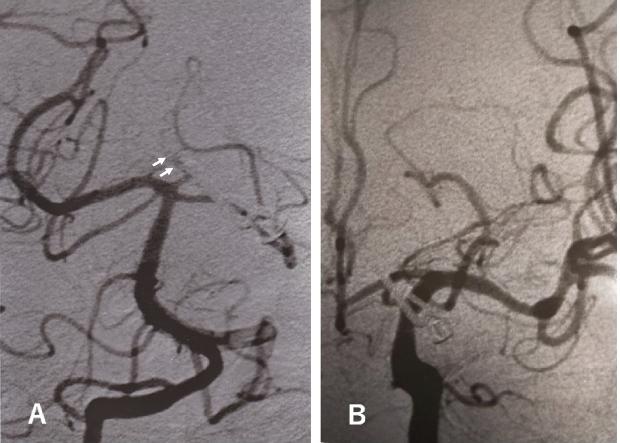

Posterior cerebral artery (PCA) aneurysms are rare and often fusiform. We describe two cases of complex proximal PCA aneurysm in two women in their 60's, which probably resulted from segmental arterial degeneration. Both presented with subarachnoid hemorrhage and had common angiographic and intraoperative findings: tortuous configuration of the affected P1 segment, whitish or yellowish appearance of a portion of the lesion, lesion calcification, and multiple aneurysms in the segment. Interestingly, no significant atherosclerotic changes were noted in other cerebral arteries. The ruptured aneurysm could be successfully trapped, with superficial temporal artery (STA)-PCA bypass in one and without bypass in the other, and both patients recovered well. As complex aneurysm formation in the cases described here are probably related to proximal PCA segmental degeneration, we recommend trapping the lesion, with or without STA-PCA bypass, depending on the size and patency of the posterior communicating artery.

大脑后动脉(PCA)动脉瘤很少见,且常呈梭形。我们描述了两例 60 多岁女性的复杂近端 PCA 动脉瘤,可能是节段性动脉退变所致。两者均表现为蛛网膜下腔出血,且具有共同的血管造影和术中发现:受累 P1 段的迂曲形态、病变部分的灰白色或黄色外观、病变钙化和节段内的多个动脉瘤。有趣的是,其他脑动脉未见明显动脉粥样硬化改变。破裂的动脉瘤可以成功夹闭,其中一例行颞浅动脉(STA)-PCA 旁路,另一例则不行旁路,且两名患者均恢复良好。由于此处描述的复杂动脉瘤形成可能与近端 PCA 节段性退变有关,因此我们建议根据后交通动脉的大小和通畅情况,夹闭病变,或行 STA-PCA 旁路。